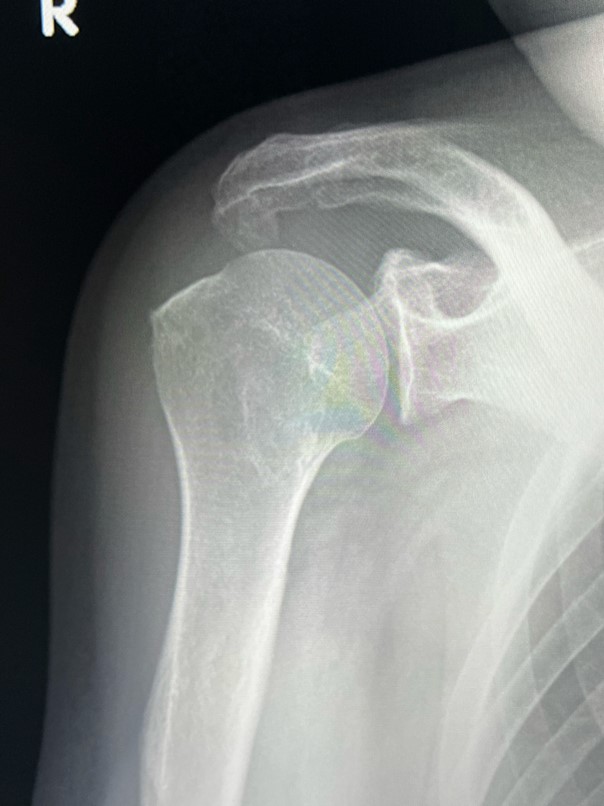

오십견 진단을 위한 필수 평가

오십견 진단을 위해서는 의사의 철저한 평가가 필요합니다. 환자의 병력, 증상, 신체검사뿐만 아니라, 필요에 따라 X-ray나 MRI와 같은 이미징 검사를 시행합니다. 신체검사는 어깨의 운동 범위를 측정하고 통증의 위치를 확인하는 과정으로, 이를 통해 오십견의 존재 여부와 정도를 파악합니다. 정확한 진단은 적절한 치료 계획 수립에 필수적입니다.